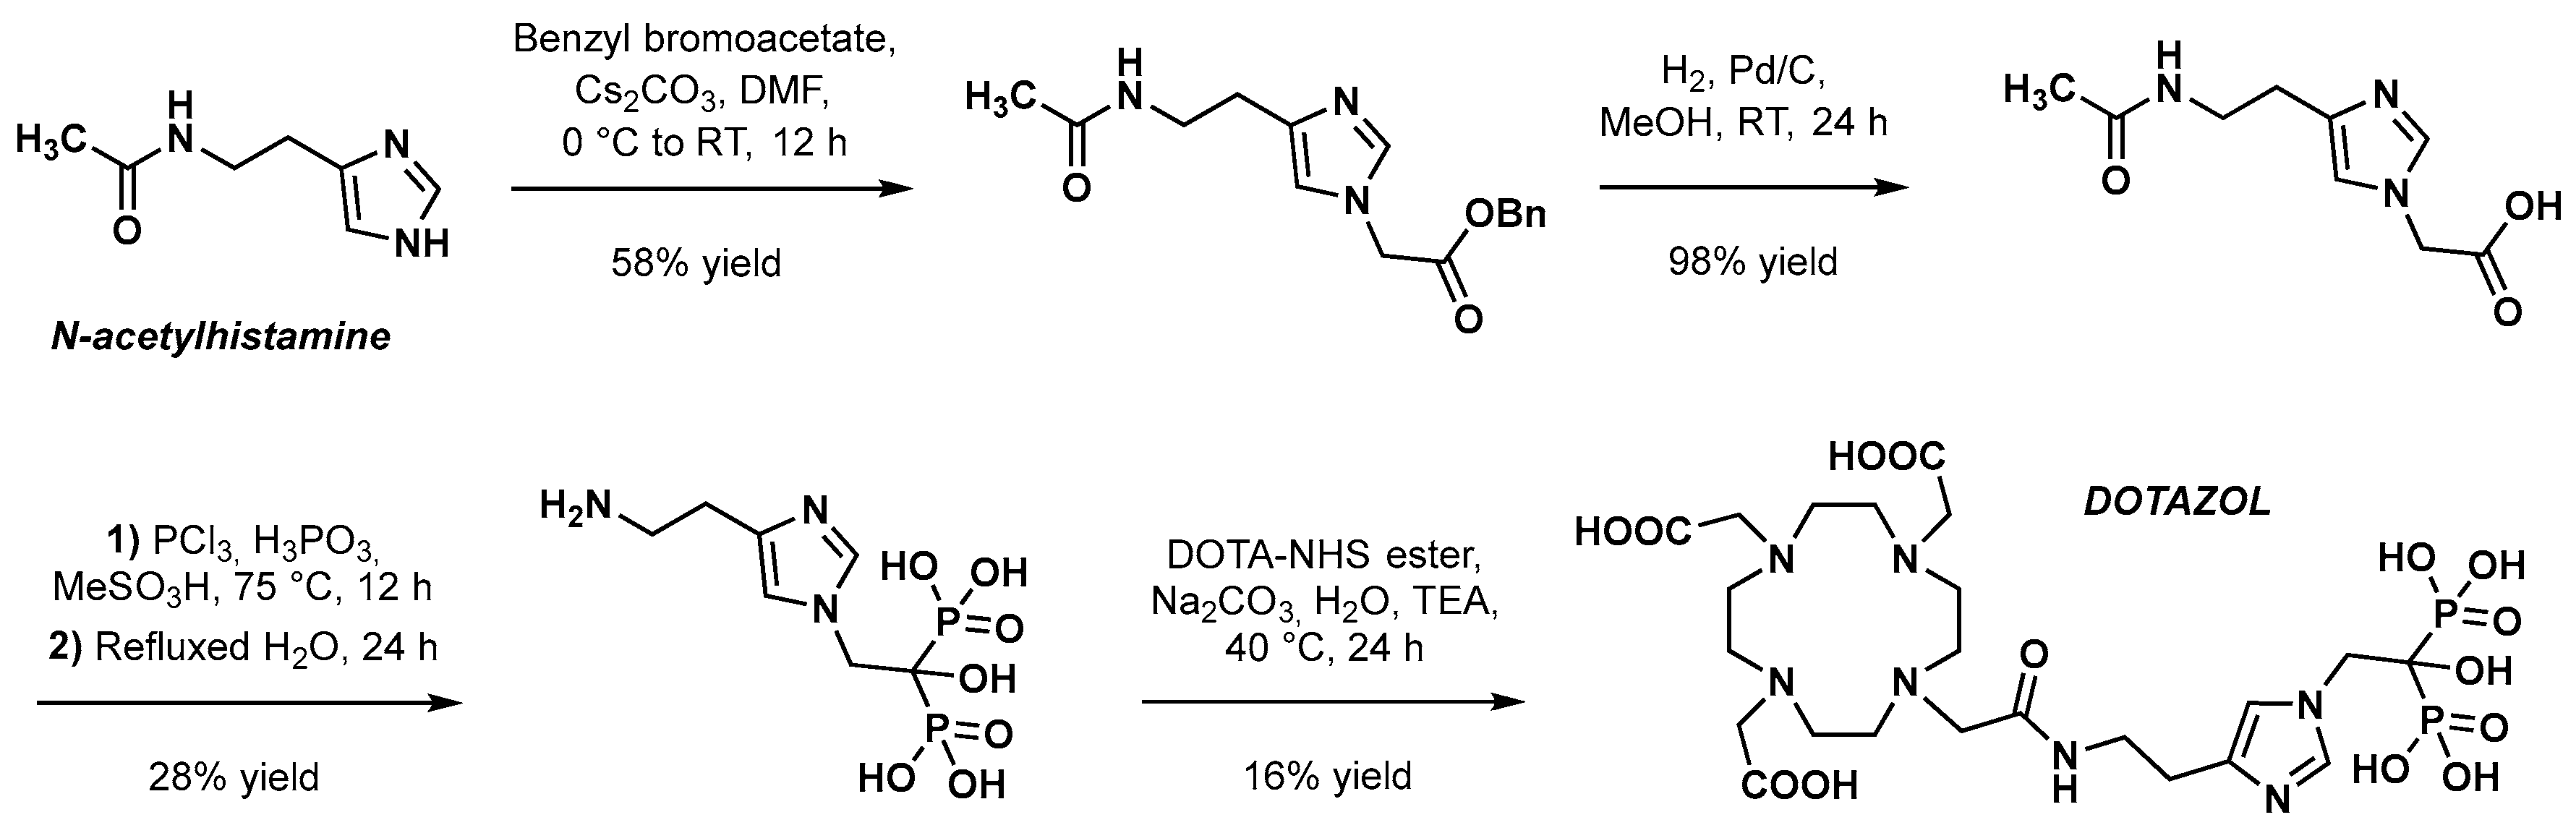

5.1. PET Imaging with [68Ga]Ga-DOTAZOL

- Lawal, I.O.; Mokoala, K.M.G.; Mahapane, J.; Kleyhans, J.; Meckel, M.; Vorster, M.; Ebenhan, T.; Rösch, F.; Sathekge, M.M. A Prospective Intra-Individual Comparison of [68Ga]Ga-PSMA-11 PET/CT, [68Ga]Ga-NODAGAZOL PET/CT, and [99mTc]Tc-MDP Bone Scintigraphy for Radionuclide Imaging of Prostate Cancer Skeletal Metastases. Eur. J. Nucl. Med. Mol. Imaging 2021, 48, 134–142. [Google Scholar] [CrossRef]

- Khawar, A.; Eppard, E.; Roesch, F.; Ahmadzadehfar, H.; Kürpig, S.; Meisenheimer, M.; Gaertner, F.C.; Essler, M.; Bundschuh, R.A. Preliminary Results of Biodistribution and Dosimetric Analysis of [68Ga]Ga-DOTAZOL: A New Zoledronate-Based Bisphosphonate for PET/CT Diagnosis of Bone Diseases. Ann. Nucl. Med. 2019, 33, 404–413. [Google Scholar] [CrossRef]